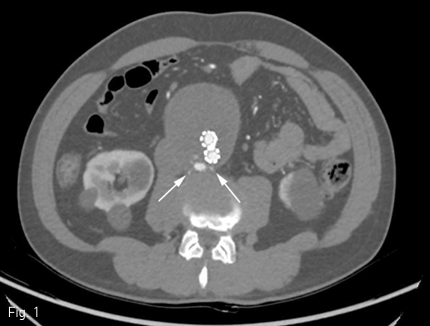

인조혈관 스텐트설치술 후 6개월뒤 시행한 CT에서 복부대동맥에서 양측 총장골동맥까지 인조혈관스텐트가 삽입되어 있었고 스텐트 삽입 전 시행한 CT 와 비교하였을 때 복부대동맥류의 크기가 최대 직경 75mm로 증가하였으며 제3 허리동맥으로부터의 type II endoleak 이 대동맥류 내에서 관찰되고 있었음. (Fig. 1)

Fig 1

CT after stent-graft insertion shows type II endoleak and retrograde flow from the right and left lumbar arteries (white arrows)